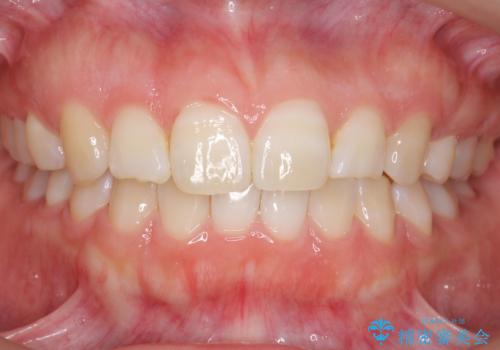

ワイヤーによる抜歯矯正でガタガタと深いかみ合わせの改善